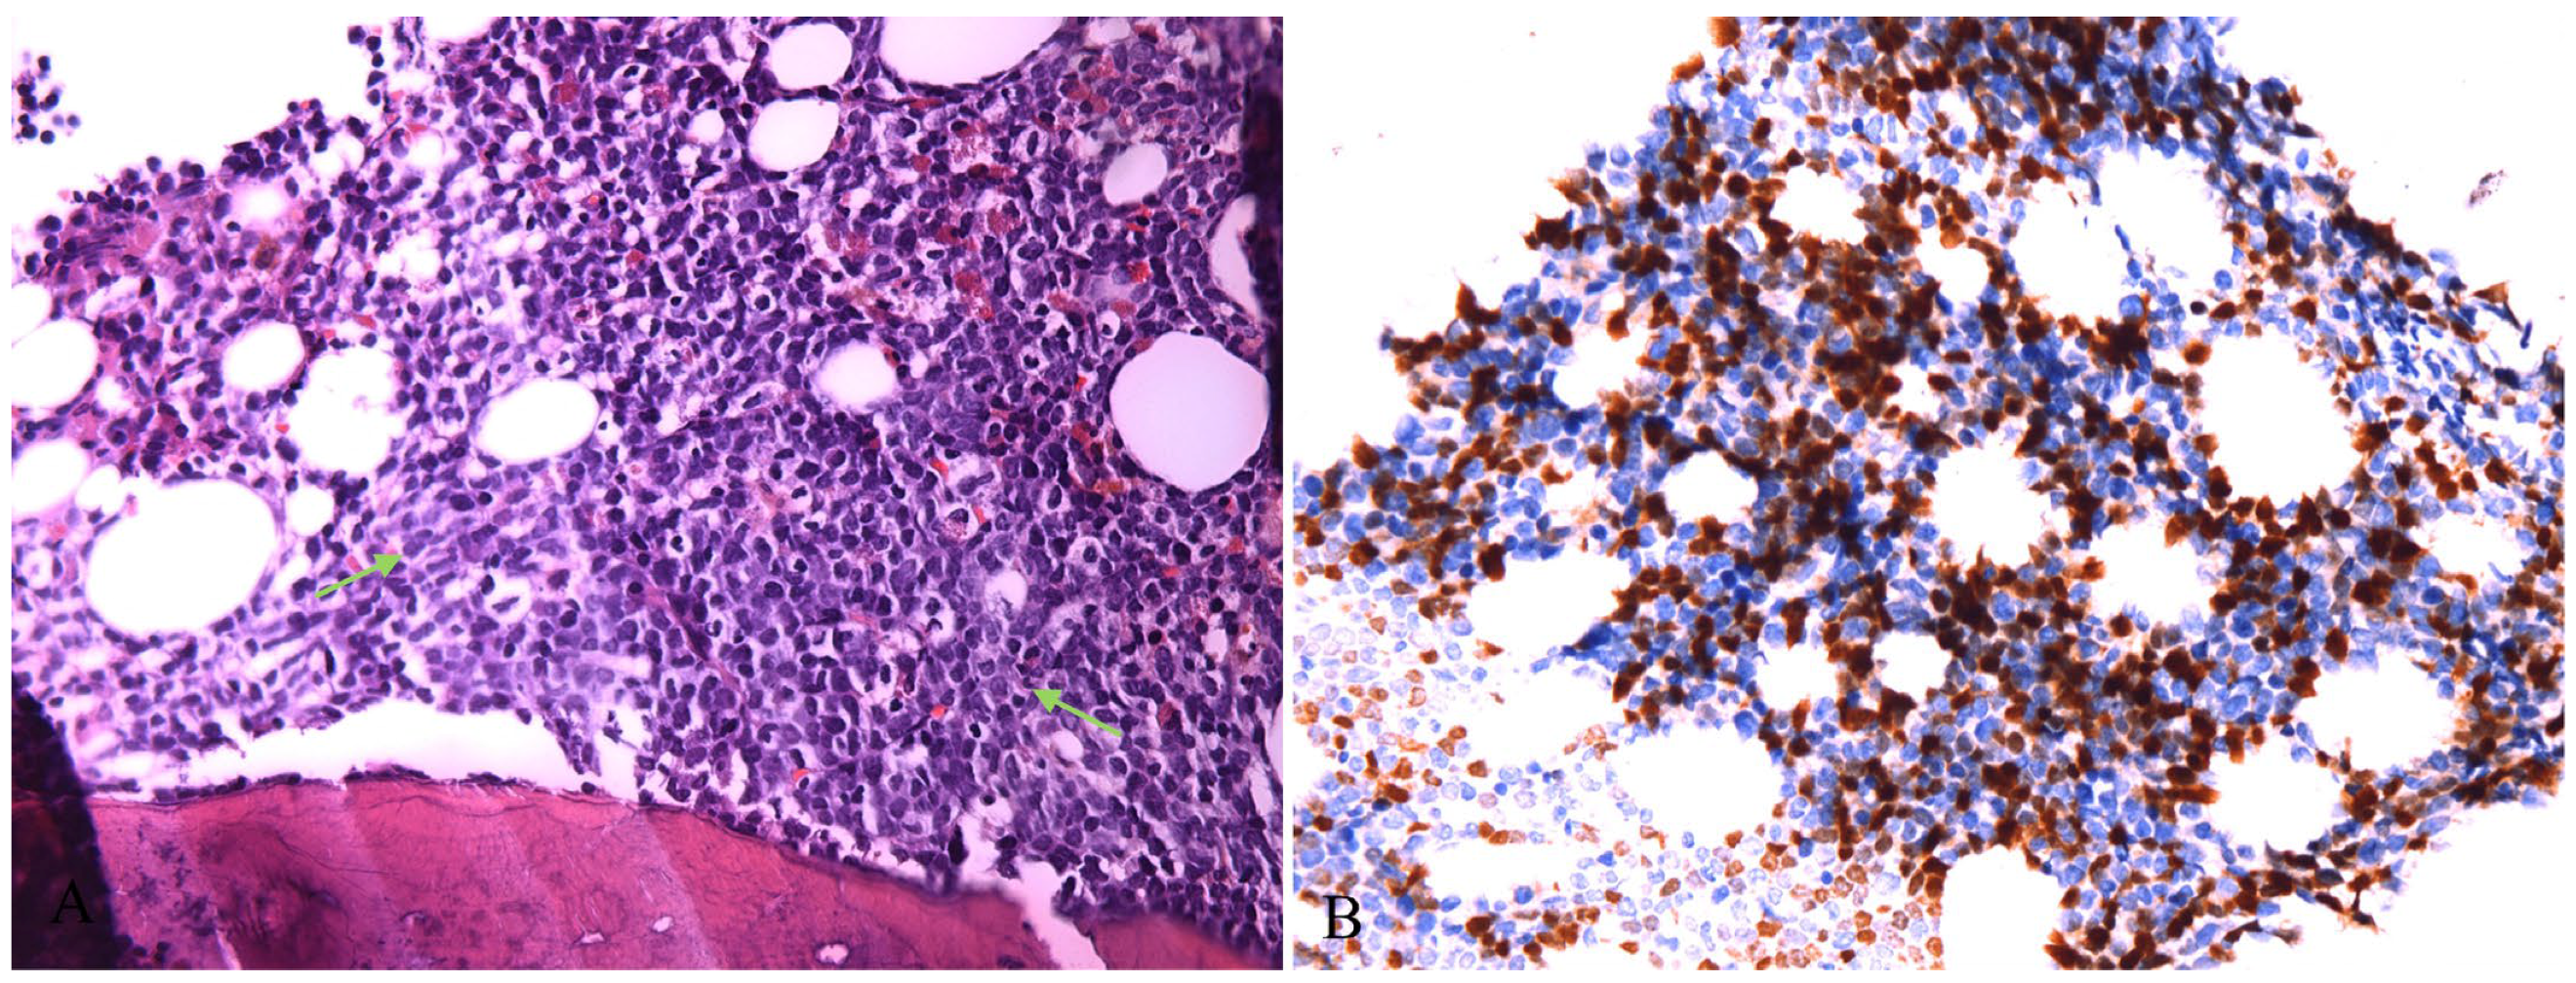

2. Case Presentation